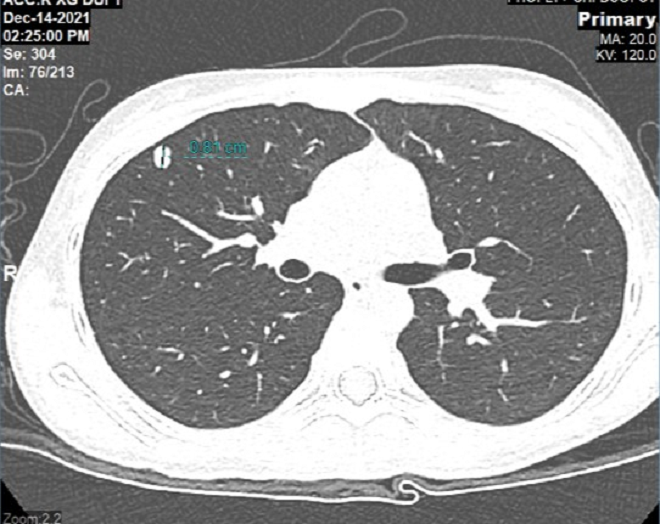

Cháu Khánh Thơ, 12 tuổi phát hiện ung thư xương chày chân trái giai đoạn 2B từ giữa năm 2021. Sau khi phẫu thuật cắt bỏ toàn bộ khối u ở khớp gối, bảo tồn chi, cháu điều trị hóa chất bổ trợ 4 chu kỳ. Tuy nhiên, chỉ hơn 1 năm sau, bé Thơ đã di căn phổi.

Tìm hiểu về quá trình điều trị của bệnh nhân, GS.TS.BS Trần Trung Dũng - GĐ Trung tâm Chấn thương Chỉnh hình và Y học thể thao (CTCH) Vinmec cho biết, mặc dù bệnh nhân có kết quả mổ rất tốt, nhưng sử dụng hóa trị bổ trợ không đủ liều là nguyên nhân dẫn đến di căn phổi nhanh như nhiều trường hợp khác.

Hình chụp CT phối của cháu Khánh Thơ phát hiện khối u di căn phổi sau 1 năm phẫu thuật cắt bỏ u khớp gối.